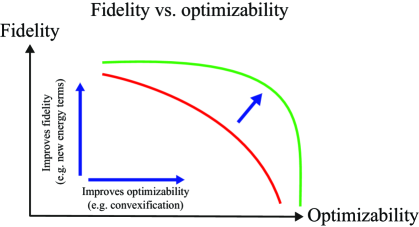

3.5 Fidelity vs. Optimizibility

In energy-based segmentation problems there is a trade-off between fidelity and optimizability (Hamarneh, 2011; McIntosh and Hamarneh, 2012; Ulén et al., 2013; Nosrati and Hamarneh, 2014). Fidelity describes how faithful the energy function is to the data and how accurate it can model and capture intricate problem details. Optimizability refers to how easily we can optimize the objective function and attain the global optimum.

Generally, the better the objective function models the problem, the more complicated it becomes and the harder it is to optimize. If we instead sacrifice fidelity to obtain a globally optimizable objective function, the solution might not be accurate enough for our segmentation purpose.

In the image segmentation literature, many works have focused on increasing the fidelity and improving the modeling capability of objective functions by (i) adding new energy terms, e.g. edge, region, shape, statistical overlap and area prior terms (Gloger et al., 2012; Shen et al., 2011; Andrews et al., 2011b; Bresson et al., 2006; Pluempitiwiriyawej et al., 2005; Ayed et al., 2009, 2008); (ii) extending binary segmentation methods to multi-label segmentation (Vese and Chan, 2002; Mansouri et al., 2006; Rak et al., 2013); (iii) modeling spatial relationships between labels, objects, or object regions (Felzenszwalb and Veksler, 2010; Liu et al., 2008; Rother et al., 2009; Colliot et al., 2006; Gould et al., 2008); and (iv) learning objective function parameters (Alahari et al., 2010; Nowozin et al., 2010; Szummer et al., 2008; McIntosh and Hamarneh, 2007; Kolmogorov et al., 2007).

Other works chose to improve optimizibility by approximating non-convex energies with convex ones (Lellmann et al., 2009; Bae et al., 2011a; Boykov et al., 2001; Chambolle et al., 2008).

An ideal method improves both optimizibility and fidelity without sacrificing either property (green contour in Figure 5).